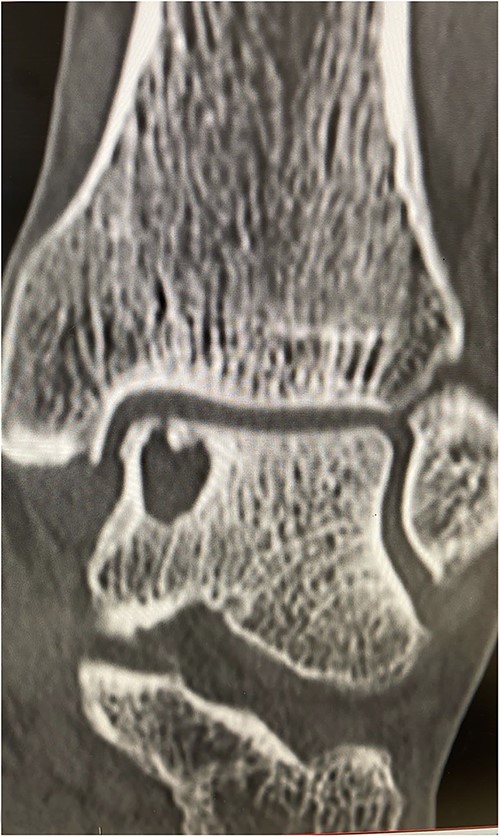

He presented with no relevant medical history and worked as a chemical plant supervisor, which required continuous movement throughout the day. Clinical examination revealed deep-seated pain around the medial aspect of the ankle with an intact range of motion and ankle alignment. His MOXFQ score was 48/80. CT scan revealed a large but well-contained, subchondral cyst in the medial talus of the ankle (Fig. 4).